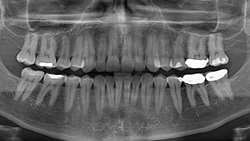

اهمیت تجویز صحیح رادیوگرافی‌های دندانی در تشخیص دقیق و حفظ سلامت

رادیوگرافی‌های دندانی در تشخیص دقیق و حفظ سلامت اهمیت تجویز صحیح رادیوگرافی‌های دندانی در تشخیص دقیق و حفظ سلامت بیماران متخصص رادیولوژی دهان، فک و صورت و عضو هیأت علمی دانشکده دندانپزشکی دانشگاه علوم پزشکی کاشان، با تأکید بر نقش کلیدی تصویربرداری صحیح...